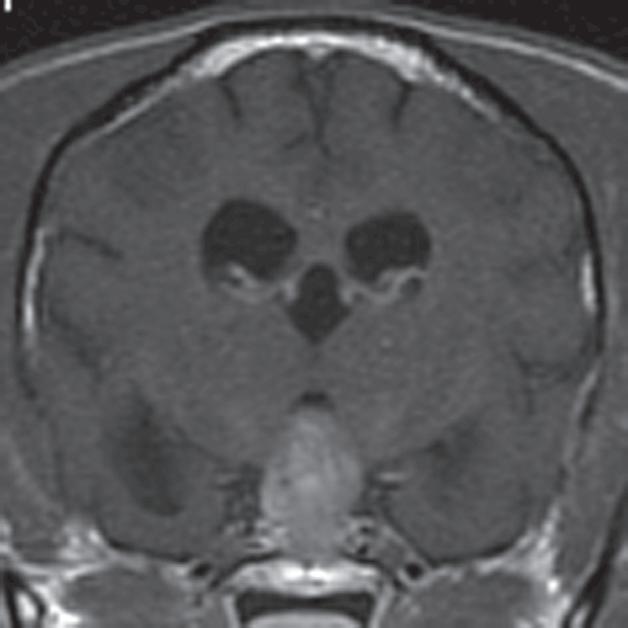

Rycina 2.9.12. Gruczolak przysadki (pies) MR

Badanie wykonano u 14-letniej, kastrowanej samicy szpica z przechyleniem głowy i występującym od niedawna chodzeniem w kółko w prawą stronę. Ryciny a–c to reprezentatywne obrazy w płaszczyźnie poprzecznej na poziomie dołu przysadki. Ryciny d–f to analogiczne obrazy w płaszczyźnie strzałkowej. Przysadka mózgowa była znacznie powiększona (wysokość = 10 mm, szerokość = 10 mm), izointensywna w obrazach T1-zależnych (a, d) i łagodnie hiperintensywna w obrazach T2-zależnych (b, e) w porównaniu z istotą szarą głęboką. Stwierdzono również poszerzenie układu komorowego (wentrikulomegalię), które może wynikać z częściowej niedrożności. Przysadka uległa jednorodnemu wzmocnieniu kontrastowemu (c, f), a w badaniu pośmiertnym wykazano, że miała postać dobrze odgraniczonej, kulistej masy (g). Potwierdzono, że zmiana była makrogruczolakiem przysadki